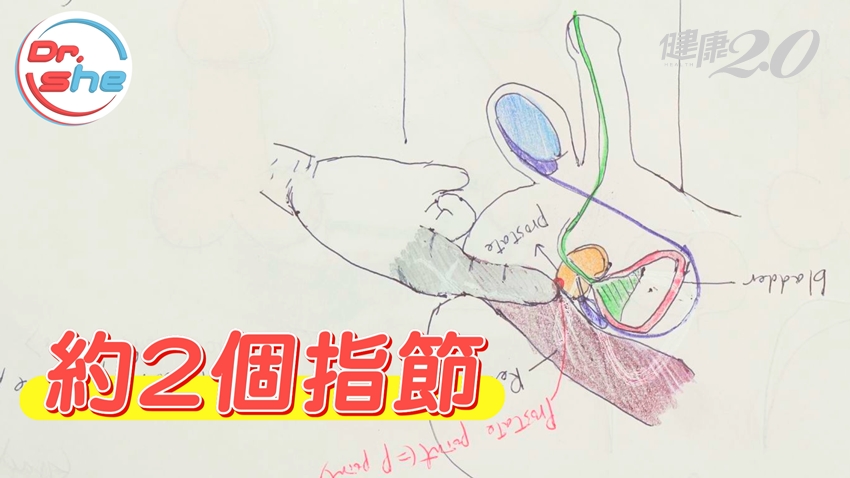

男性敏感帶6:P點

P點俗稱是「男性的G點」,也就是攝護腺點,可以使用水性潤滑液,將手指進入肛門內約2個指節處,摸起來像是栗子,只要輕柔畫圈,就會有敏感的感覺。但是,P點高潮時,龜頭只會有分泌物,並不會射精。